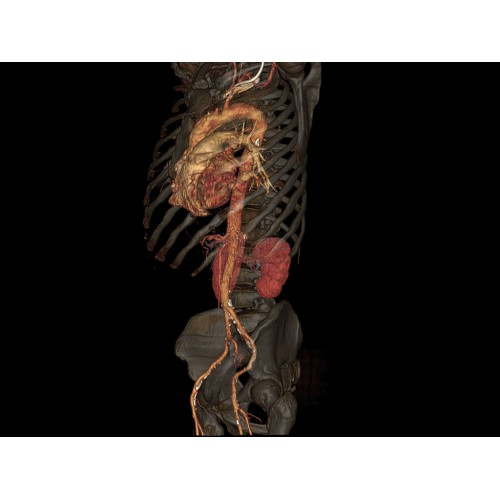

Современный КТ аппарат GE Optima CT520 – это инновационное оборудование для точной и быстрой диагностики. Он сочетает в себе передовые технологии, надежность и удобство использования, что делает его востребованным в медицинских учреждениях различного профиля.

• Высокое качество изображения благодаря усовершенствованной системе реконструкции данных.

• Широкая область применения: от неврологии до кардиологии и онкологии.

• Неинвазивная оценка состояния коронарных артерий.

• Диагностика атеросклероза и других сердечно-сосудистых патологий.

• 3D-реконструкция костных структур для планирования операций.